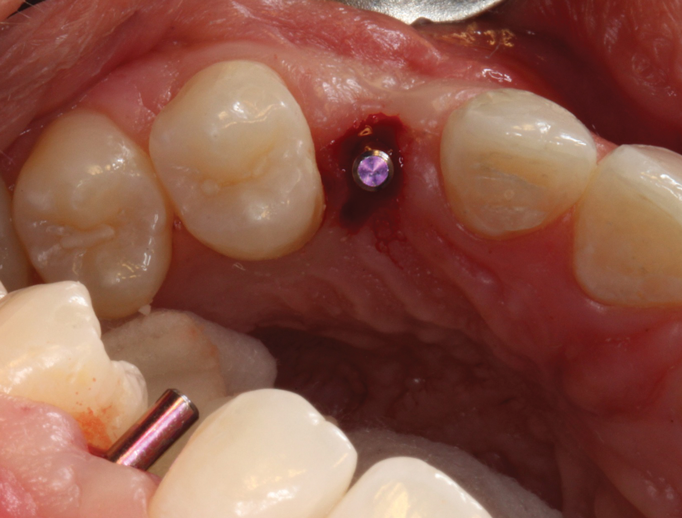

(46.) Occlusal view of the implant after placement.

Figure 46

(47.) The primary stability of the implant was confirmed to be sufficient for immediate loading.

Figure 47